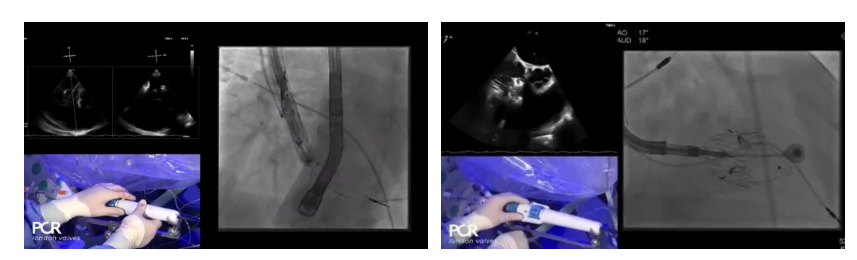

在Thomas Modine教授的線上指導下,德國Mainz中心Ralph Stephan von Bardeleben教授完成了LuX-Valve Plus經血管三尖瓣置換系統在其所在中心的首例植入,術后Stephan教授高度贊揚LuX-Valve Plus人工三尖瓣瓣膜“植入過程高度可控,安全有效”。接受治療的是一例82歲的高齡男性患者,術前NYHAⅢ級,因復發心衰入院,有逾5年的慢性房顫病史。這例患者因特殊的解剖結構以及較大的三尖瓣瓣環,有起搏器植入史,被所有其他經導管三尖瓣修復或置換器械的臨床排除在外,因此等了一年半才等到此次LuX-Valve Plus的手術機會,實屬不易。

手術在全麻狀態下開展,采用經右側頸靜脈入路的方式將輸送器送入患者心臟內,在TEE及DSA引導下調整輸送器頭端角度,使得輸送器與三尖瓣瓣環平面垂直。在輸送器進入右心室后釋放室間隔錨定裝置,而后釋放瓣葉夾持件(2個耳片結構)成垂直狀態。在TEE及DSA確定夾持件固定至三尖瓣葉根部且位于右室側后釋放人工瓣心房側盤片。隨后調整瓣膜同軸性以及室間隔錨定件位置(貼合室間隔),前推藏針管并固定,進而釋放室間隔錨定裝置,并再次確認瓣膜位置、穩定性及同軸性,合攏輸送鞘后撤出輸送器,完成LuX-Valve Plus人工三尖瓣瓣膜的植入。